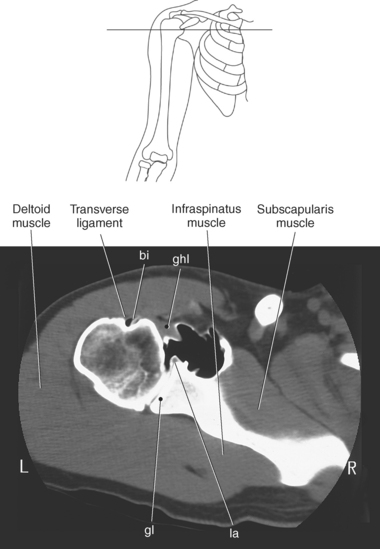

The edge of the glenoid fossa is surrounded by a fibrocartilaginous ring termed the glenoid labrum (glenoid lip) (Figure 9.17). The glenoid labrum is a fold of the articular capsule, which functions to deepen the articular surface of the glenoid fossa. Superiorly, the labrum blends with the long head of the biceps brachii muscle. In cross section it appears triangular (Figure 9.18). The three glenohumeral ligaments (superior middle, and inferior) are thickenings of the fibrous capsule that surrounds the shoulder joint; they contributes to the formation of the glenoid labrum (Figures 9.17 and 9.19). They extend from the supraglenoid tubercle of the scapula to the lesser tubercle of the humerus. Also aiding in strengthening the fibrous capsule is the coracohumeral ligament that passes from the lateral side of the coracoid process of the scapula to the anatomic neck of the humerus (Figure 9.19). The coracoacromial ligament is another important ligament located on the anterior portion of the shoulder. As this ligament joins the coracoid process and acromion, it forms a strong bridge, termed the coracoacromial arch, which protects the humeral head and rotator cuff tendons from direct trauma and prevents displacement of the humeral head superiorly (Figures 9.17 and 9.19). The coracoclavicular ligaments help to maintain the position of the clavicle, in relation to the acromion, by spanning the distance between the clavicle and coracoid process of the scapula (Figure 9.19). The acromioclavicular ligament, at the acromioclavicular joint, provides support for the superior surface of the shoulder (Figures 9.17 and 9.19). The transverse humeral ligament is a broad band of connective tissue passing from the greater tubercle to the lesser tubercle of the humerus, forming a bridge over the intertubercular groove for protection of the long head of the biceps tendon (Figure 9.19). The ligaments of the shoulder are demonstrated in Figures 9.20 through 9.30.

Muscles of the scapula are described in Table 9.2 and demonstrated in Figures 9.34 through 9.52. The large deltoid muscle originates on the clavicle, acromion, and scapular spine to blanket the shoulder joint as it extends to insert on the deltoid tuberosity of the humerus. This powerful muscle forms the rounded contour of the shoulder and functions primarily to abduct the arm (Figure 9.48). The teres major muscle is a flat rectangular muscle that adducts and medially rotates the arm. It extends from the inferior angle of the scapula to the medial aspect or lip of the intertubercular groove of the humerus (Figure 9.49, A). The four remaining muscles, supraspinatus, infraspinatus, teres minor, and subscapularis, closely surround the scapula and compose the rotator cuff (Figures 9.49 through 9.52). The rotator cuff provides dynamic stability to the shoulder joint and allows for adduction, abduction, and rotation of the humerus. The supraspinatus, infraspinatus, and teres minor muscles are located on the posterior aspect of the scapula. The tendons of these muscles insert on the greater tubercle of the humerus. The supraspinatus muscle lies in the supraspinous fossa of the scapula and helps to abduct the arm. The tendon of the supraspinatus muscle is the most frequently injured tendon of the rotator cuff because of possible impingement as it extends under the acromioclavicular joint and continues over the humeral head (Figure 9.49, B). The infraspinatus muscle is a triangular muscle that lies below the scapular spine in the infraspinous fossa. It acts to laterally rotate the arm (Figure 9.49, A). Lying along the inferior border of the infraspinatus muscle is the elongated teres minor muscle, which also acts to laterally rotate the arm (Figure 9.49, B). The subscapularis muscle is the only muscle of the rotator cuff located on the anterior surface of the scapula; its tendon inserts on the lesser tubercle of the humerus (Figures 9.50 through 9.52). The subscapularis muscle acts to medially rotate the humerus. See sequential images through the shoulder (Figures 9.34 through 9.47).